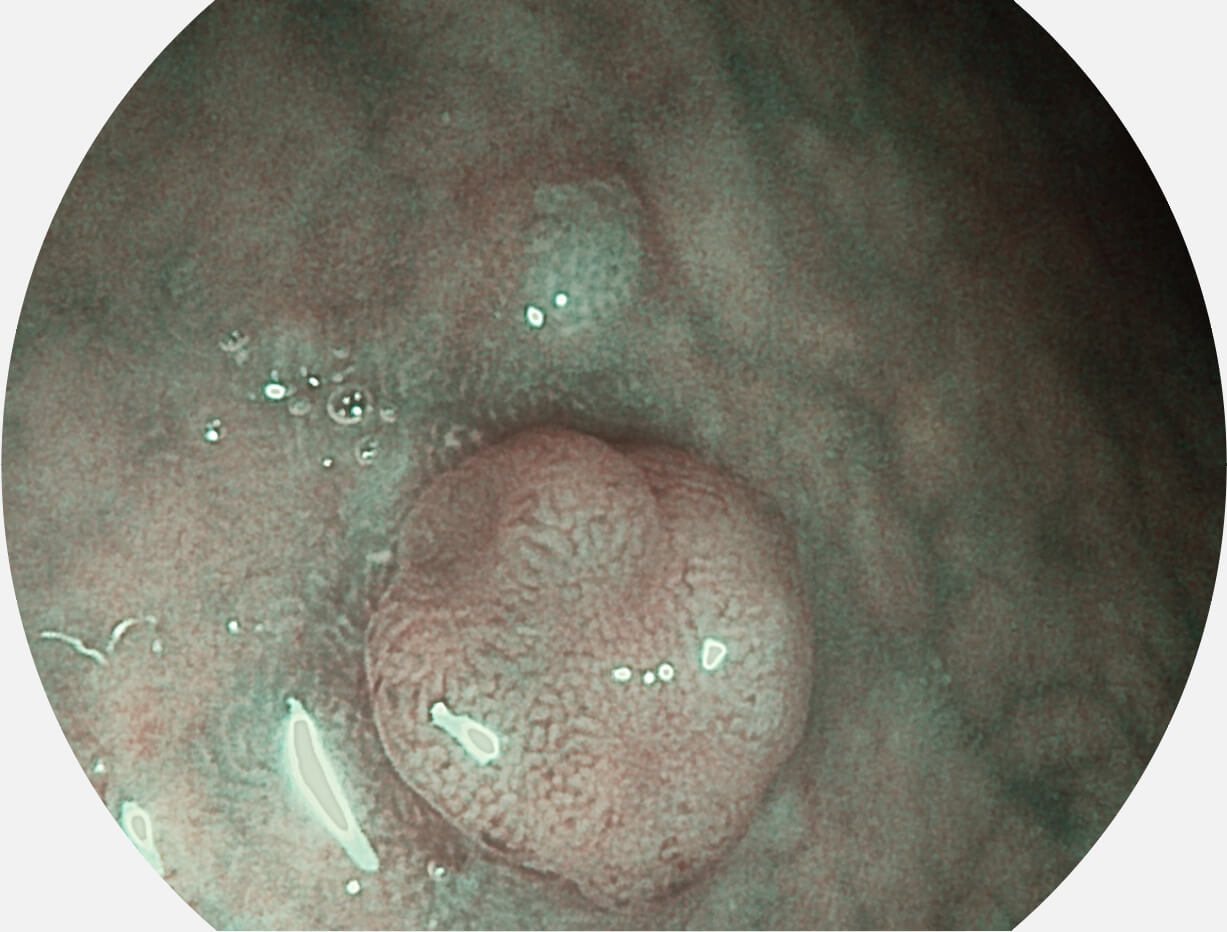

强调浅层黏膜结构的同时,保证照明亮度和提升浅层微血管与中层血管颜色对比度,病变边界更清晰。

白光图像

VIST图像